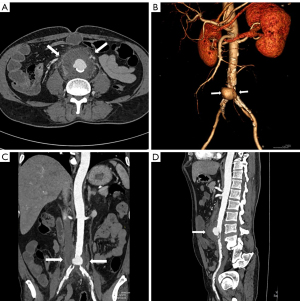

Four months later, while doing laundry, the patient inadvertently moistened the infusion port, resulting in local redness, swelling, fever, and pain lasting three days. The highest recorded body temperature exceeded 39°. After self-administering antipyretic medication, the fever subsided. Ten days later, the patient experienced lower back and abdominal pain. A contrast-enhanced CT scan of the chest and abdominal was performed, revealing a reduction in the primary lung lesion and mediastinal lymph nodes compared to previous imaging (Figure 1). The images showed disruption of the abdominal aortic wall and a saccular pseudoaneurysm with rim enhancement of periaortic thickened soft tissue, indicating a mycotic abdominal aneurysm (Figure 2). Notably, Staphylococcus aureus was detected in blood cultures. Therefore, the patient was hospitalised and underwent open abdominal aortic artificial vessel replacement surgery. Postoperative pathology demonstrated the absence of normal aortic wall structure, with fibrous inflammatory exudate and abscess lesions (Figure 3). The postoperative recovery was good, and the patient was subsequently discharged. No lung cancer-related treatment was provided following the artificial vascular graft replacement surgery.

Three months later, the patient experienced vomiting accompanied by dizziness and unstable walking. A brain MRI revealed multiple intracranial metastases, while an enhanced abdominal CT scan identified multiple masses around the artificial graft in the retroperitoneal abdominal aorta, in the left gluteal muscle gap, and adjacent to the right iliac artery. Pathological findings from the puncture of lesions in the left gluteal muscle space suggested poorly differentiated adenocarcinoma (Figure 4). It was considered that metastasis was concentrated around the artificial graft in the abdominal aorta, with biopsy pathology confirming poorly differentiated adenocarcinoma of lung origin. The patient did not receive any subsequent tumor-related treatment.